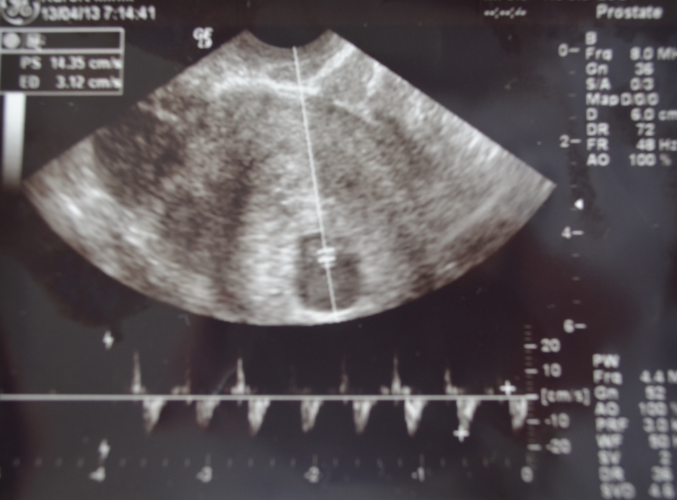

Наше первое УЗИ (12.04.13-7 нед)

УЗИ, КТГ, доплерВот сходила я на УЗИ, думала рано и ещё не будет СБ,но ни фига(я слышала) всё здорово. Итак:

Тело матки - 6.4см*5.8см*5.5см

В полости матки Плодное Яйцо - СВД-18 мм

Эмбрион - КТР- 8 мм

ЧСС - 143 ударов в минуту

Желточный мешок - СВД - 5 мм

Заключение: БЕРЕМЕННОСТЬ - 7 НЕДЕЛЬ.